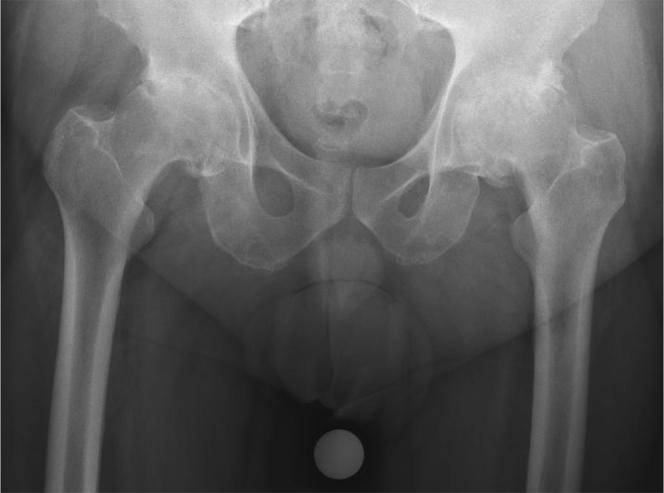

Hip osteoarthritis typically manifests with groin or thigh pain. Other atypical pain patterns, including knee pain, have been described. Except for 2 case reports, there is no literature on this subject.

From our institutional database, between 2011 and 2016, we identified 21 patients who were referred for treatment of knee pain but ultimately diagnosed with hip pathology as the cause of their pain. This group was evaluated for duration of symptoms prior to diagnosis, previous interventions, presence of walking aids, and symptom resolution after treatment of the hip pathology.

Fifteen of the 21 patients were referred from musculoskeletal providers (12 from orthopaedic surgeons). Prior to diagnosis of the hip etiology, 16 patients were reduced to major assistive devices including wheelchairs. Twelve of 21 patients had undergone surgical knee interventions, including total knee arthroplasty, with minimal to no relief of their pain. Seventeen of 21 referred patients underwent total hip arthroplasty at our institution. Fourteen patients had complete resolution of knee pain after total hip arthroplasty.

Although knee pain referred from hip disease may be considered a basic and common knowledge, it continues to be an overlooked phenomenon. Most of the cases were misdiagnosed by musculoskeletal providers including orthopaedic surgeons and this highlights the need for continued education and awareness of this clinical scenario.